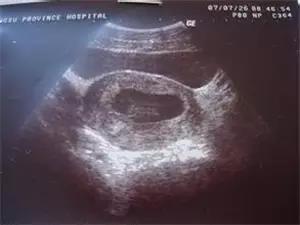

原則上在孕40天時(shí),我們就可以通過陰道超聲,觀察到宮內(nèi)的孕囊,在孕45天時(shí),看到胚芽和胎心搏動(dòng)。

如果此時(shí)血清HCG >1000 IU ~ 1500 IU,B超還沒有看到宮內(nèi)的典型孕囊,異位妊娠的可能性>95%,需要留院觀察,動(dòng)態(tài)超聲檢查,看輸卵管和其它部位是否出現(xiàn)孕囊和胎心。

因此,在這個(gè)懷孕階段,不要拒絕超聲檢查,即使HCG的檢測(cè)水平只有幾百單位,B超沒有見到宮內(nèi)孕囊,都要密切觀察是否宮外孕可能。

胚胎停止發(fā)育的診斷比起宮外孕的診斷要容易得多,早孕期血清HCG水平低下,翻倍試驗(yàn)異常,B超觀察到宮內(nèi)有孕囊,有的也看到胚芽和卵黃囊,但在孕45~50天還沒有見到胎心搏動(dòng),延長(zhǎng)觀察了1~2周,還未見胎心。